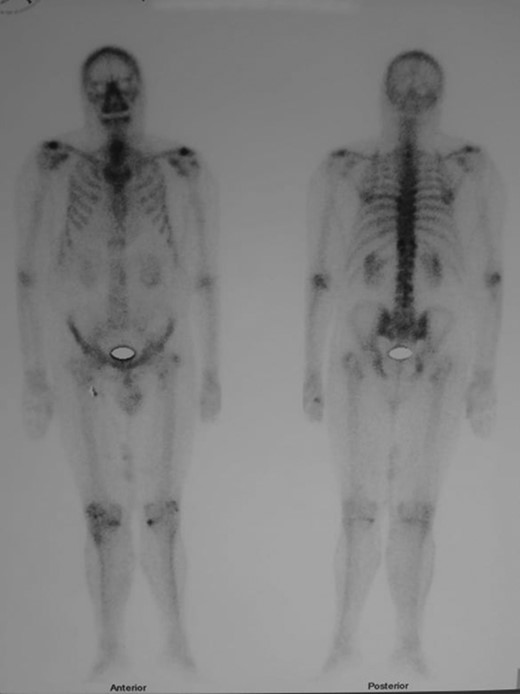

Forty-five days after surgery, the patient received adjuvant oral 100 mCi 131I. A total body SPECT scan 6 days after treatment did not show any areas of abnormal distribution (Fig. 5). During the following month, the patient was also administered 30 doses of external beam radiation therapy (EBRT).

Total body SPECT scan performed after adjuvant radioiodine treatment. No abnormal distribution is observed.